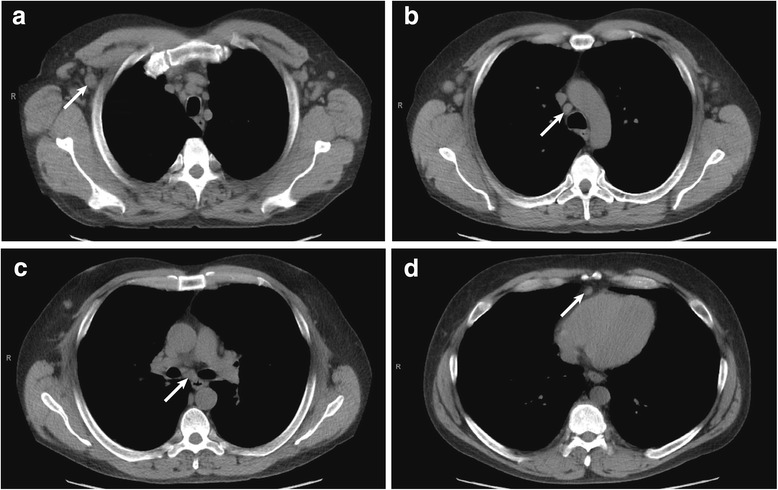

A 47-year old Caucasian man with history of depression and remote polysubstance abuse presented to his primary care physician with two months of cough, dyspnea, and asthenia. Chest radiography demonstrated patchy, diffuse interstitial infiltrates. Chest computed tomography (CT) disclosed diffuse lymphadenopathy, splenomegaly, and bilateral bronchiectatic changes (Figure 1). Body positron emission tomography (PET)/CT showed diffuse, hypermetabolic (mild-moderate 18 F-fluorodeoxyglucose (FDG) uptake) lymphadenopathy without other evidence of malignancy. The initial differential diagnosis included atypical respiratory infection, granulomatous disease, and lymphoproliferative disorder. He underwent bronchoscopy with bronchoalveolar lavage, with negative staining for acid-fast bacilli, no malignant cells on cytology, and no growth in bacterial and fungal cultures. Transbronchial lung biopsy revealed non-specific chronic inflammation, and fine needle aspirate of a left neck lymph node was non-diagnostic. A repeat bronchoscopic evaluation nine months later was similarly unrevealing. Serum protein electrophoresis showed no evidence of monoclonal gammopathy, and angiotensin-converting enzyme levels were within normal limits. Serum inflammatory markers were elevated (erythrocyte sedimentation rate 111 mm/hr, C-reactive protein 7.28 mg/dL), but an extensive biochemical evaluation for infectious etiologies, including HIV, tuberculosis, coccidioidomycosis, aspergillosis, cryptococcosis, blastomycosis, and histoplasmosis, was negative. Due to an elevated Strongyloides IgG antibody titer, he was treated with ivermectin but had no improvement in his symptoms.

Figure 1.

Lymphadenopathy on chest CT. Chest CT demonstrating enlarged lymph nodes (arrows) involving the right axillary (a), paratracheal (b), subcarinal (c), and cardiophrenic (d) regions.